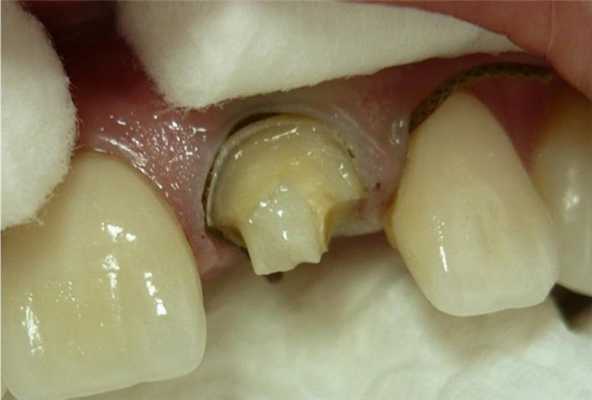

3 этап. Фиксация коронки на восстановленную культю зуба.

Материалы используемые для адгезивной техники фиксации: адгезив All Bond 3, праймер для оксида циркония, алюминия и металла Z-PRIMER PLUS, композитный цемент светового отверждения Choice 2

Я использую адгезивную фиксацию для коронки из оксида алюминия. Для этого внутренняя поверхность коронки из оксида алюминия пескоструится с применением порошка оксида алюминия 50 мкр при давлении до 2 атм. под непрямым углом к поверхности.

Обезжиривается в спирте или ацетоне, просушивается. На внутреннюю поверхность коронки наносится праймер для оксида циркония и алюминия Z-PRIMER PLUS (Bisco IL, USA) несколько слоев на 30 секунд. Высушивается. Поверхность коронки готова.

Вновь созданная культя зуба подвергается адгезивному протоколу: протравливается, наносится адгезив All Bond 3, полимеризуется. В коронку вносим композитный цемент светового отверждения. Коронка адаптируется на культе зуба. Излишки цемента подвергаются 2 секундной полимеризации, убираются с краев коронки и проводится транскоронковая полимеризация с каждой стороны по 30 секунд.